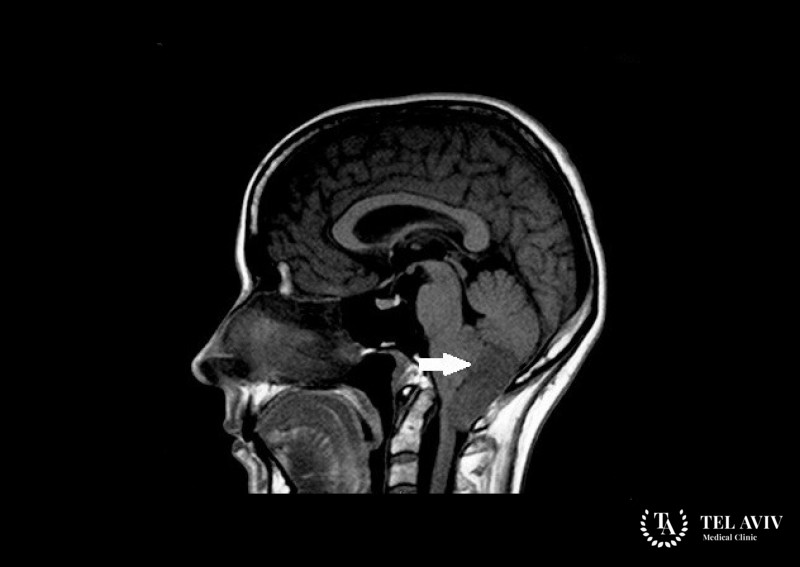

Эпендимома – является злокачественной опухолью ЦНС, которая состоит из ткани, выстилающей изнутри желудочки головного мозга и центральный канал спинного мозга. Данная патология является крайне опасной и может прорасти в соседние структуры и ткани. Человек может не подозревать о наличии заболевания на начальном этапе, так как симптоматика выражена кране слабо. Зачастую опухоль возникает из-за распространения метастаз по телу. Заболевание врач может обнаружить у взрослого любого возраста. Необходимо немедленно приступить к его лечению во избежание возникновения нежелательных осложнений.

В ведущей израильской клинике работает настоящая команда профессионалов, которая занимается выявлением и лечением опасных патологий головного мозга у взрослых, в частности эпендимомы IV желудочка. Мы используем оригинальные препараты и новейшее оборудование. Наши хирурги используют малоинвазивные способы хирургического вмешательства, которые являются наиболее эффективными и малотравматичными.